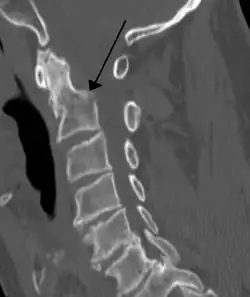

Bei einem Genickbruch – einem Bruch des Zahns des zweiten Halswirbels (Dens axis) – oder einem Riss der Bänder des Dens axis können das verlängerte Mark (Medulla oblongata) und das Rückenmark durchtrennt oder abgequetscht werden. Kommt es dabei zu einer Zerstörung des Atem- und des Kreislaufzentrums, so hat dies den sofortigen Tod zur Folge, vergleichbar einer Enthauptung. Besteht bei Verletzten ohne Spontanatmung der Verdacht auf eine Fraktur des Dens axis, so muss eine notwendige Intubation mit Vorsicht in Neutralstellung der Halswirbelsäule vorgenommen werden, um mögliche oder weitere Schädigungen von verlängertem Mark bzw. Rückenmark zu vermeiden.[2] Rund 70 Prozent der Genickbrüche gehen mit einer Schädigung des Rückenmarks (im Halsbereich) einher, was bei Überlebenden zu dauerhaften Lähmungen führen kann (wie z. B. einer Tetraplegie). Dagegen gibt es auch heilbare Genickbrüche, die – bei korrekter Behandlung – keine dauerhaften Folgeschäden nach sich ziehen.[3]

Die Bänder kann man auf Röntgenbildern weder sehen noch beurteilen, daher werden sie bei einem Röntgenbefund meist nicht erwähnt. Ein dorsales knöchernes Atlantodentalgelenk gibt es also nicht, sondern nur eine hintere Gelenkfläche des Dens axis, die mit dem Ligamentum transversum atlantis artikuliert. Aufschluss über Position und Zustand von Dens und Axis liefert oft eine Röntgenaufnahme bzw. eine MRT, anhand deren auch etwaige Fehlbildungen ausgeschlossen werden können. Im Zuge der Röntgendiagnostik wird eine Aufnahme des Dens mit anterior-posteriorem Strahlengang vorgenommen und bei einem auffälligen Atlantodentalgelenk eine MRT der HWS. Zeigt sich hierbei ein unauffälliges Atlantodentalgelenk – gleichgültig ob eine Asymmetrie nach links oder rechts vorliegt, da dies eine häufige Normvariante ohne medizinische Relevanz darstellt –, liegt keine Instabilität der Kopfgelenke vor.[6]